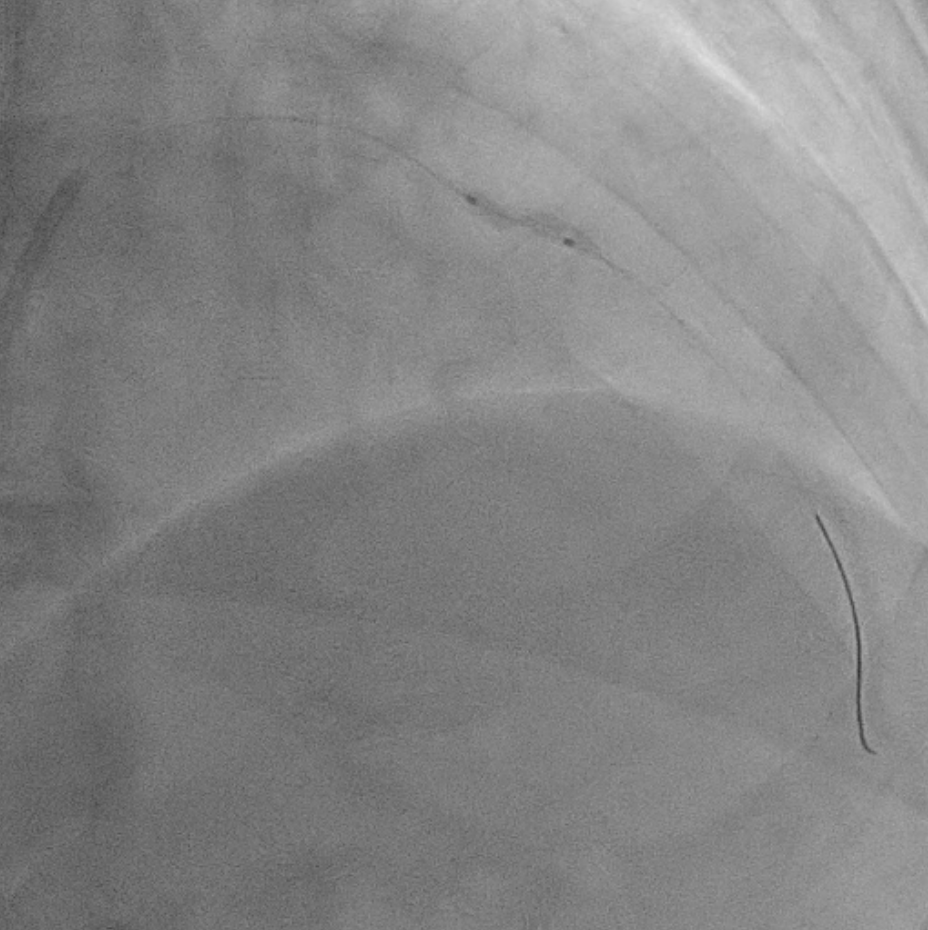

Two months ago, PCI of the LAD wasattempted. The guidewire successfully crossed to the distal LAD, but a 2.5 mmscoring balloon could not cross the mid lesion and showed a ¡°dog-bone¡±appearance upon inflation, so the procedure was stopped, and PCI of the LCx wasperformed instead. We reattempted PCI of the LAD using a Mach CLS 7 Fr guidingcatheter. A Fielder XT wire crossed to the distal LAD, but the OCT cathetercould not cross the lesion. Lesion preparation with a 2.0 mm scoring balloon athigh pressure and a 2.0 mm Wolverine cutting balloon enabled OCT passage. OCTimaging revealed fibrous and nodular calcification in the mid LAD, with aminimal lumen area of 1.71 mm and reference diameters of 4.0 mm (proximal) and3.3 mm (distal). Orbital atherectomy using a Diamondback 360 (1.25 mm crown)was performed carefully due to vessel tortuosity, with 10 runs at80,000–120,000 rpm. Post-atherectomy OCT showed reduced calcium burden andincreased lumen area. Further lesion preparation with 2.5 and 2.75 mm scoringballoons showed no ¡°dog-bone¡± sign, indicating adequate calcium fracture. A 3.0¡¿ 46 mm Amphilimus DES was implanted in the proximal–mid LAD and post-dilatedwith a 3.5 mm NC balloon. Final angiography showed TIMI 3 flow withoutdissection. Post-stent OCT showed good apposition, MSA 8.84 mm©÷ proximally and5.73 mm©÷ distally, with 99% expansion. The patient remained hemodynamicallystable and was discharged the following day.